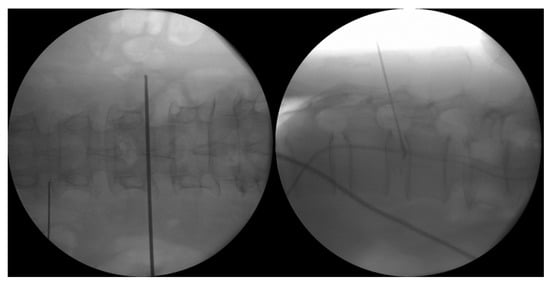

4.1.1. Interlaminar Endoscopic Lumbar Approach to Disc

4.1.3. Transforaminal Endoscopic Lumbar Approach for Radiofrequency Ablation

4.2. Ablation of Neuropathic Basivertebral Nerve and Sinuvertebral Nerve